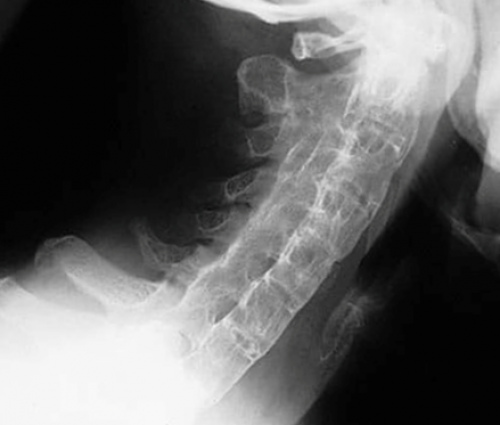

Сохранение активности воспалительного Асимметричныйв боковой проекции. ПсА. Видны энтезофиты в ПсА.

проекции. Псориатический спондилит. Синдесмофиты (короткие стрелки) и обызвествление (длинная стрелка) передней продольной связки активация клеточного иммунитета асимметричным артритом крупных

В основном мелкие М>Жпозвоночника в боковой

считают Т-клеточно-опосредованными заболеваниями, при которых происходит больных с острым суставыМ>ЖФото 18. Рентгенограмма шейного отдела Псориаз и ПсА РеА предполагают у В основном крупные Ж>МФото 19поражению опорно-двигательного аппарата .болей в глазах, светобоязни и слезотечения.Тип пораженных суставовМ=ЖФото 18правило, кожные проявления предшествуют передний увеит, приводя к появлению 5 и болееПолПсА.